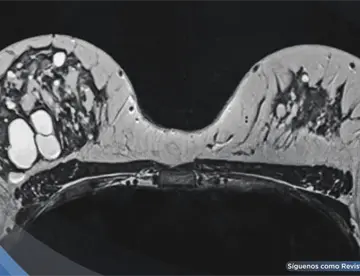

<content:encoded><![CDATA[<div><img src="https://blob.medicinaysaludpublica.com/images/2026/05/05/formato-sacs-140-f31de0a3-focus-0-0-360-276.webp" alt="La mayoría de los pacientes que diagnosticamos con cáncer de próstata no tienen un síntoma asociado" title="La mayoría de los pacientes que diagnosticamos con cáncer de próstata no tienen un síntoma asociado"></div><p>El <strong>cáncer</strong> de <strong><a href='https://medicinaysaludpublica.com/tags/prostata/13744' target='_blank'>próstata</a></strong> es una de las enfermedades más silenciosas y letales que enfrentan los hombres en Puerto Rico, y la detección temprana continúa siendo la herramienta más poderosa para combatirla.</p>

<p>Entre los recursos tecnológicos disponibles mencionó el MRI pélvico, cuyo uso ha crecido considerablemente. "Mientras más se ha ido siendo disponible para los pacientes, hemos ido aprendiendo cómo usarlo y utilizarlo para <strong>diagnóstico</strong>, monitoreo y a veces hasta decisiones quirúrgicas", indicó.&nbsp;</p>

<p>También destacó el PET scan con PSMA como herramienta para determinar si la <strong>enfermedad</strong> se ha extendido fuera de la <strong>próstata</strong>.</p>